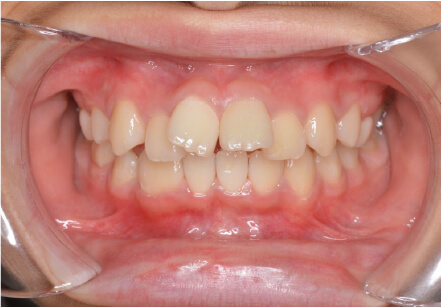

11歳

女性

上の前歯の歯並びが気になる(マイオスマイルからの移行)

インビザライン、拡大入れながらスペースを作成、下Eは出てきたら削りながら進める

全額アライナー矯正 クリアコレクト

クリアライナー使用

痛み・歯根吸収・歯肉退縮・虫歯・後戻り

移行料金220,000円、月々16,500円、1年1ヶ月+myo2年3ヶ月